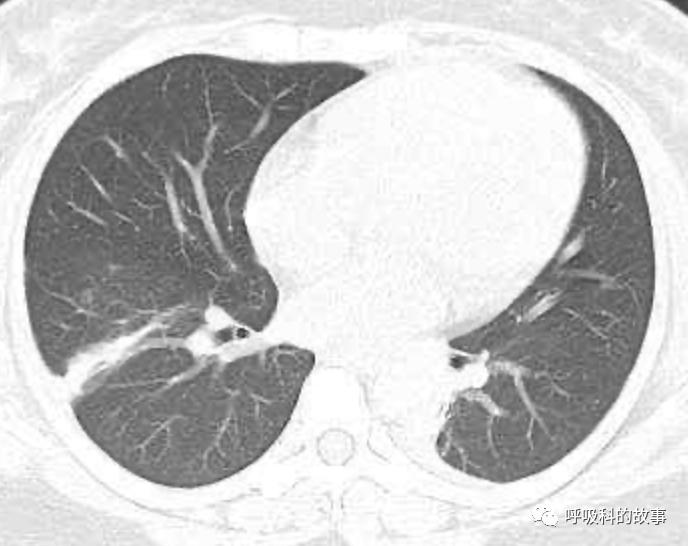

可是在6月26日(往院第18天)仍持续发热的情况下复查肺部CT,肺部病灶已明显吸收了。那么患者发热的原因到底是什么呢?为什么患者高热的情况下血白细胞不升反降,C反应蛋白也没有明显增高?这个时候消化科医生也迷茫了,这可怎么办?于是请感染科和呼吸科医生一起会诊,共商计策。